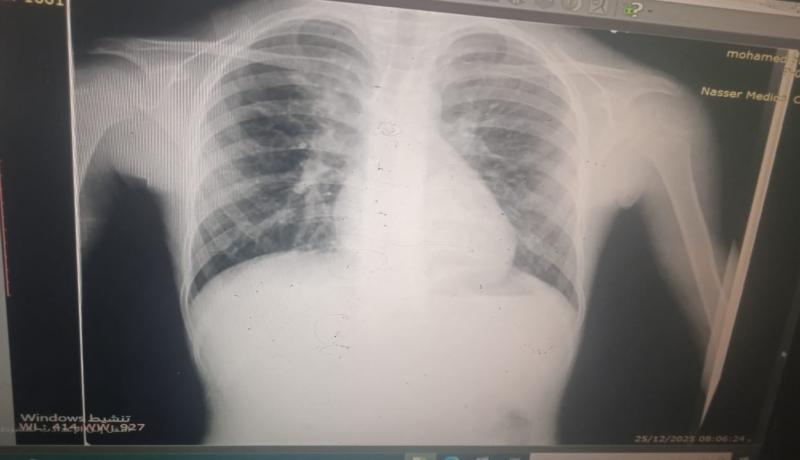

يقول والده، إن ابنه وُلد مصابًا بتشوّه خلقي يُعرف باسم "رباعية فالوت"، موضحًا أن حالته تتضمن ثقبًا متوسط الحجم بين البطينين، وضيقًا شديدًا في الصمام الرئوي، وتضخمًا في عضلة القلب اليمنى، وانحرافًا بالشريان الأورطي إلى الجهة اليمنى.

ويؤكد الوالد، أن حالة ابنه مصنّفة "A طارئ"، وأن وضعه الصحي تدهور خلال الحرب، حيث يعاني التهابات صدرية شديدة بشكل دائم، وضيقًا في التنفس، وإرهاقًا متكررًا، إضافة إلى حاجته لاستخدام البخاخ بشكل مستمر، وتعرضه لتشنجات.